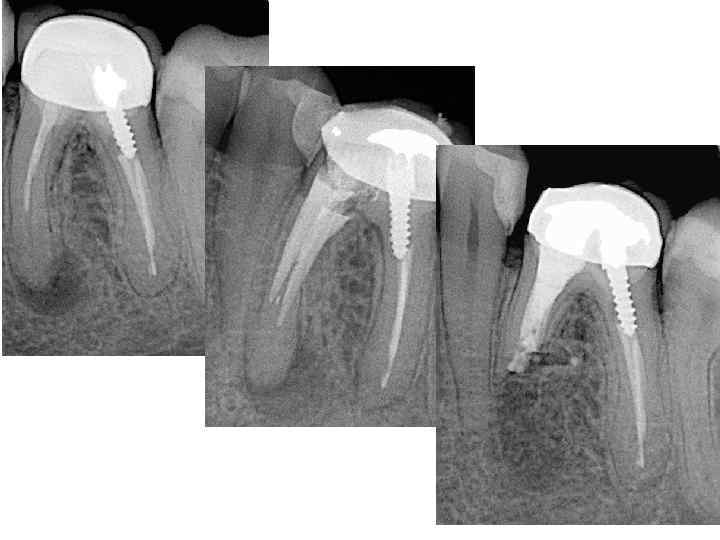

Реплантация зуба Возвращение в лунку удаленного зуба. Операцию проводят при безуспешности или невозможности консервативной терапии, нежелательности удаления зуба. Заключается в удалении зуба, выскабливании патологических тканей из альвеолы и с поверхности корня. После пломбирования каналов и резекции верхушек корней, зуб вводят в лунку и фиксируют там. Производят реплантацию преимущественно многокорневых зубов. Большое значение для успеха реплантации имеет сохранность круговой связки. Зуб удаляют осторожно, стараясь не травмировать тканей зубной альвеолы и прилегающих мягких тканей. Так же осторожно делают кюретаж альвеолы, убирая грануляционные разрастания или гранулему, стараются сохранить волокна периодонта по боковой поверхности альвеолы и круговую связку. Промывают рану теплым изотоническим раствором натрия хлорида с добавлением антибиотиков (грамицидин, линкомицин и др. ) и рыхло тампонируют стерильной марлей. Удаленный зуб временно помещают в какую-либо емкость, содержащую теплый (36, 6 °С) изотонический раствор натрия хлорида с добавлением антибиотиков или раствора хлоргексидина. Пломбируют полость зуба и каналы стеклоиномерным цементом, но лучше МТА цементом , создающим лучший герметизм и не влияющим токсически на костную ткань. Отпиливают верхушки его корней. Иногда корни зубов не резецируют, а только расширяют каналы и осуществляют медикаментозную обработку и их пломбирование. При этих манипуляциях осторожно держат зуб стерильной салфеткой и обязательно помещают его в консервирующий раствор (изотонический раствор натрия хлорида), После туалета кости зуб помещают в альвеолу и фиксируют его при помощи проволочной шины, защитной пластинки из быстротвердеющей пластмассы, проволочно-композитной фиксации, каппы на 2— 3 нед.

Имплантация зуба относится также к аллотрансплантации или эксплантации. Применяются титановые, реже циркониевые имплантаты. Имплантаты бывают пластиночными, винтовые(корневидные), поднадкостничные. Если имлантацию проводят при удалении зуба ее называют немедленной имплантацией.

Резекция верхушки корня зуба • показана, когда невозможно устранить хронический воспалительный процесс в периодонте консервативными методами лечения, а также в тех случаях, когда канал зуба закрыт застрявшим в нем инородным телом (головка бора, отломок пульпэкстрактора и др. ), препятствующим дальнейшему лечению периодонтита. Кроме того, она эффективна при перфорации стенки корня в верхушечном отделе, недостаточном выполнении канала твердеющим пломбировочным материалом, а также чрезмерном выведении его за верхушку, также отсутствие регресса околокорневого патологического очага, наличие свищевого хода после правильно проведенного эндодонтического лечения. В основном выполняют резекцию верхушки корня резцов и клыка, а также малых коренных зубов на нижней челюсти, реже — на верхней. В последние годы показания к этой операции расширены, и ее успешно осуществляют в области малых и больших коренных зубов.

сошлифовав фрезой несколько наискось культю корня, небольшим шаровидным бором расширяют просвет канала, затем обратно-конусовидным бором или ультразвуковой насадкой формируют в культе полость, выполняют ее серебряной амальгамой, стеклоиномерным цементом, МТА цементом, вводя небольшими порциями и конденсируя инструментом